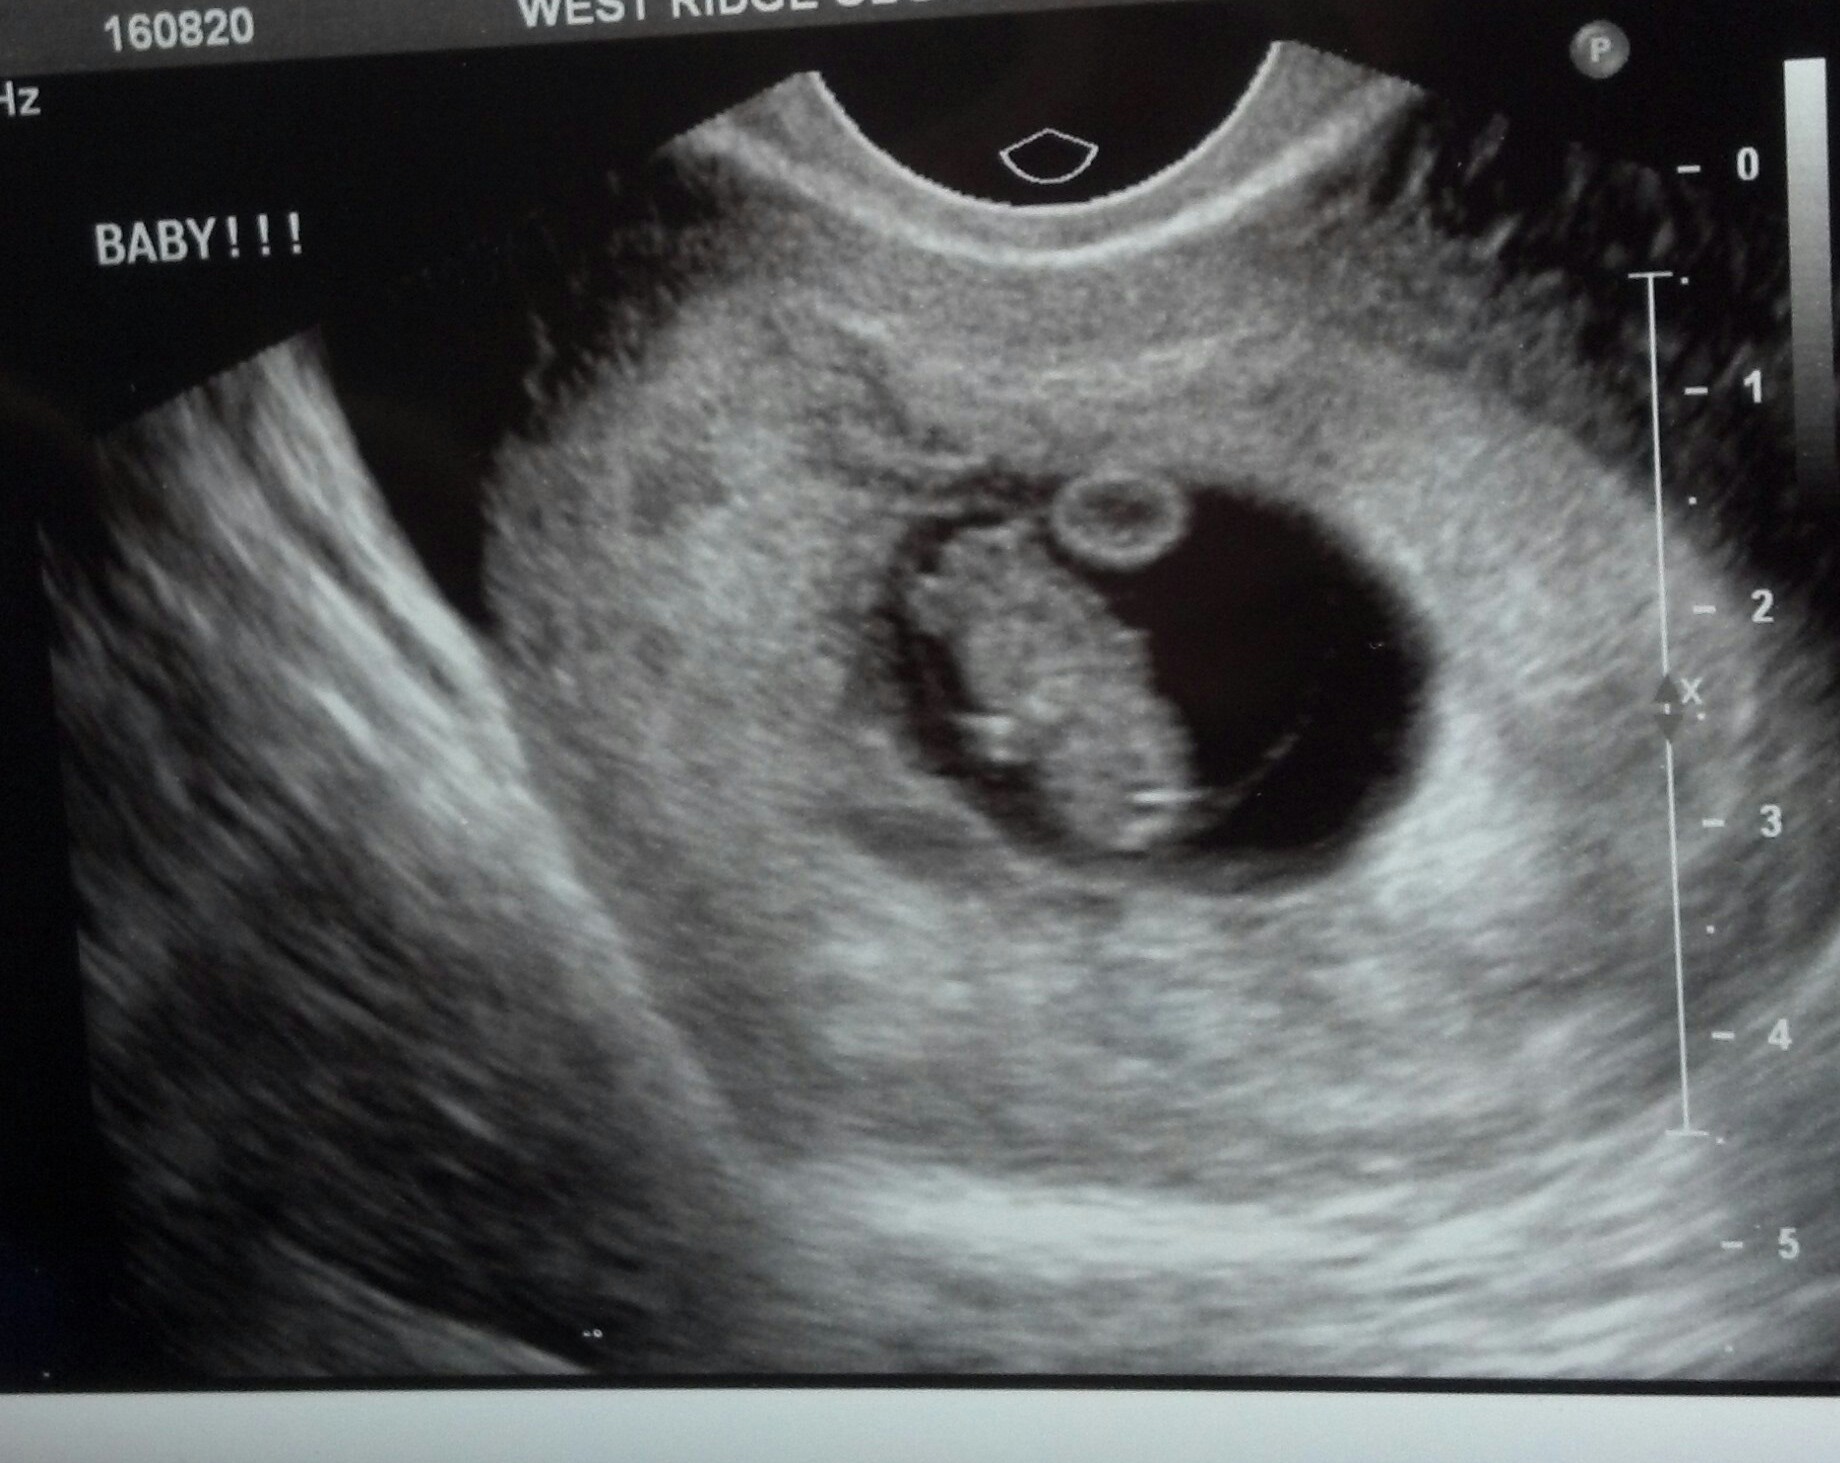

MY U/S!!!!!

I saw my little gummy bear yesterday!! :) The heart beat was 182 and I am exactly 8 weeks and 2 days along :):)

• Congrats in your little gummy bear! It looks so weird to me to see u/s with just one baby now! (Yay for twins!)

• That's why I had an U/S so early because twins run on both sides of our family so I just wanted to make sure I was having one or two....and it's just one little healthy baby! <3:)